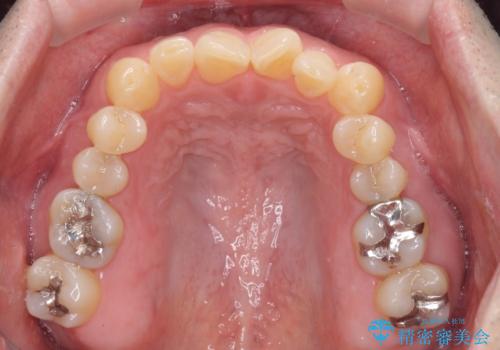

歯並びや口元の印象、奥歯の咬み合わせから、非抜歯にて矯正治療を行うこととしました。

また、左下の奥歯は親知らずの影響で手前の歯の歯根までむし歯になってしまったため、親知らずとともに抜歯をし、インプラントによる補綴治療を行うこととしました。

インプラント埋入による仮歯の装着や、前歯の反対咬合の改善は比較的スムーズに達成されましたが、舌突出癖などの影響による、歯列全体のスペースを閉じることが難航し、期間がかかってしまいました。